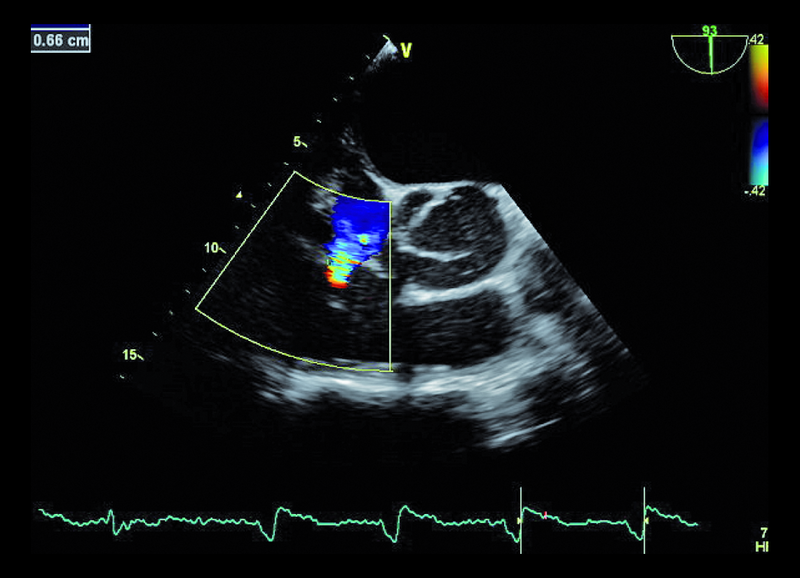

Mężczyzna, lat 68. Jakie patologie można rozpoznać na rycinach?

3. Niedomykalność zastawki trójdzielnej (ryc. 3, 4).